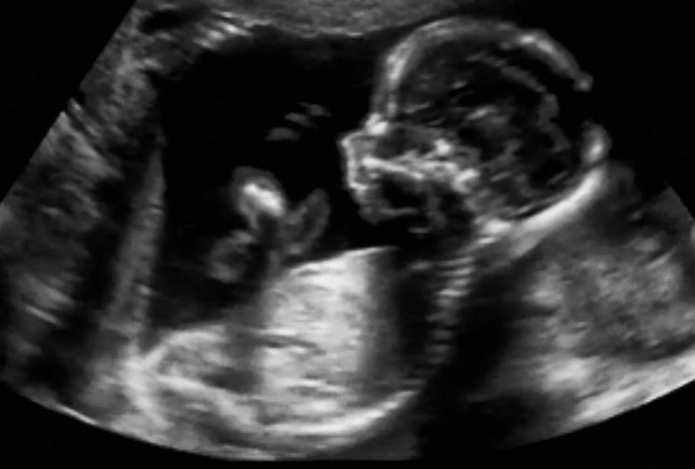

Развитие расстройства аутистического спектра (РАС) у ребенка можно предотвратить на ранних этапах развития плода, — в этом родителю может помочь фетальное программирование, рассказала «Газете.Ru» врач-психиатр, доктор медицинских наук НИИ педиатрии и охраны здоровья детей РНЦХ им. акад. Б.В. Петровского Наталия Устинова, передает Sports.kz.

«Это теория, согласно которой сигналы окружающей среды во время внутриутробного развития плода играют основополагающую роль в определении траекторий здоровья на протяжении всей жизни. В рамках этого направления выделяются управляемые факторы, которые могут повысить вероятность рождения здорового ребенка. Это базовое ведение здорового образа жизни, отказ от препаратов, которые провоцируют РАС», — отметила специалист.

Кроме того, крайне важно проводить профилактику преждевременных родов, которая включает грамотное наблюдение врача-гинеколога до родов и во время беременности.

Шведские ученые из Лундского университета выяснили, что ранние роды могут быть одной из основных причин развития РАС среди детей. Устинова отметила, что это не единственное исследование, которое подтверждает: ребенок, рожденный преждевременно, имеет повышенные риски формирования нарушений нейропсихического развития, включая аутизм, или, как принято сейчас называть это состояние, расстройства аутистического спектра (РАС).

«Важно подчеркнуть, что преждевременные роды — это, возможно, не начало, а один из этапов процесса, в результате которого и формируется РАС. Кроме того, исследования определяют общие факторы риска для недоношенности и аутизма: метаболические нарушения, сахарный диабет, дефицитное питание, высокий индекс массы тела мамы. Но связь между недоношенностью и аутизмом не означает, что одно обязательно вызывает другое. Исследователей интересуют возможные генетические факторы и факторы окружающей среды, влияющие как на преждевременные роды, так и на аутизм», — объяснила Устинова.